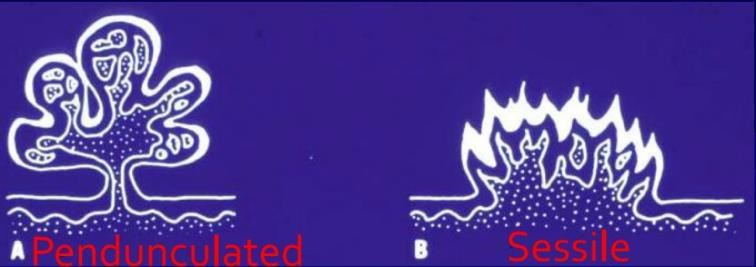

pedunculated, sessile(少)  |

- | 皮膚、口腔(少見、接觸、自傳染) | 大多是sessile(無梗) | |||